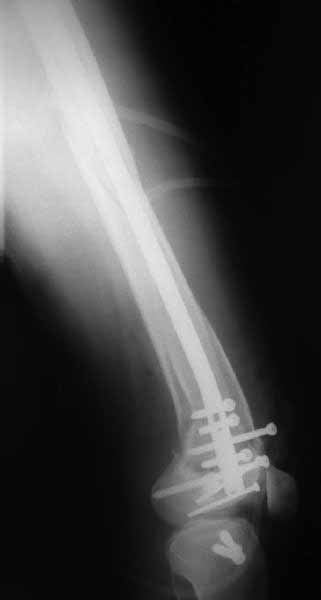

В приложении пример недавней операции, C3, открытая репозиция, фиксация мыщелков спицами и винтами, ретроградный синтез большеберцовым гвоздем 10,5 мм диаметром, винты 5 мм.

Позволю себе напомнить коллегам ещё раз, что являюсь сторонником антеградного остеосинтеза при переломах дистального эпиметафиза бедренной кости. Такая приверженность основана не на преимуществах внесуставного введения стержня или большем проценте положительных результатов. Она основана на возможности обеспечить блокирование на минимальном расстоянии от суставной поверхности в нескомпрометированной кости и, таким образом стабилизировать максимально низкие переломы. В приведенном Вами случае самый дистальный из блокирующих винтов проведен на расстоянии более 2 см от конца стержня. Из-за того, что к стержню присоединяется кондуктор, на стержне теряется 1-1,5 см его длины, где можно было разместить отверстия для блокирования. И что более важно, вместе с потерянной для этой цели длиной стержня утрачивается для размещения блокировочных винтов, пожалуй, самая ценная часть дистального эпиметафиза бедренной кости. Проблемы дистального блокирования в разных плоскостях, локализации точки ввода стержня при антеградном остеосинтезе – это всё решаемые технические проблемы. Но антеградный остеосинтез низких дистальных переломов бедра при адекватном блокировании в нескомпрометированной кости обеспечивает решение стратегической задачи – стабильный остеосинтез и возможность нагрузки.

В приведенном Вами случае самый дистальный из блокирующих винтов проведен на расстоянии более 2 см от конца стержня.

На этом большеберцовом стержне центр ближайшего к кондуктору отверстия в 14 мм от конца. И пример был про то, что пластина тут, скорее всего, была бы не худшим выбором.